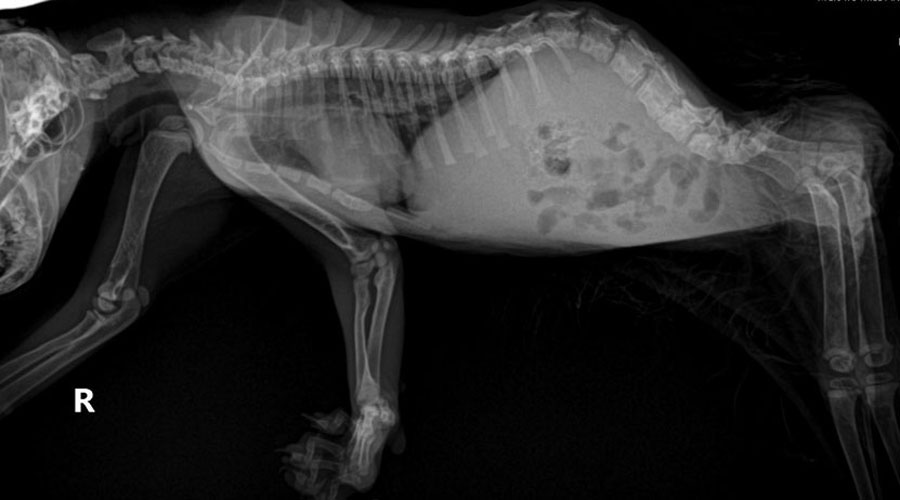

Each of these three represents a different cause of the bladder and bowel deficits which make the special needs care for all the cats at Familiars Surrounding necessary.